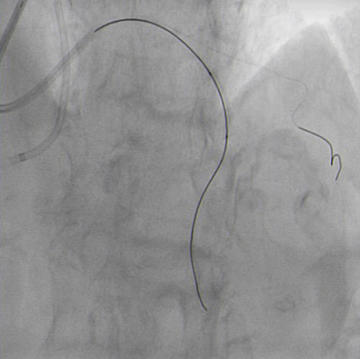

Double radial access with guiding catheter 6F JR 4.0 and sheatless 7.5F PB 3.5. Controlateral injection to check antegrade wire position via collaterals (Figure 4.1).

Antegrade guide wire position (Figure 4.1)

CTO crossed with Miracle 6g, after unsuccessful attempts with Sion and Pilot 150. Floppy wire in diagonal branch to improve support (Figure 4.2).

Guide wires to LAD and diagonal branch (Figure 4.2)